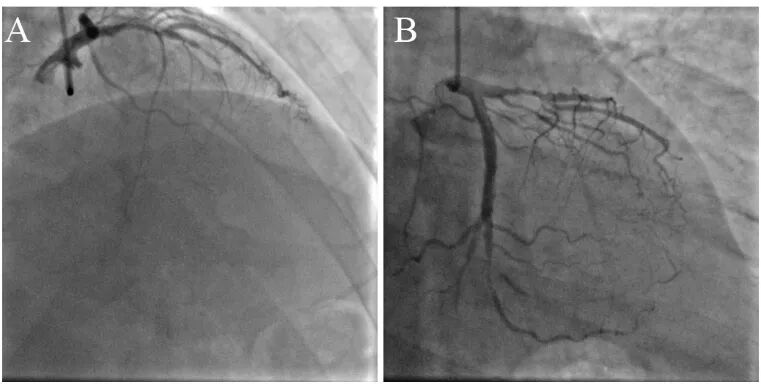

入院后冠状动脉造影显示前降支近段狭窄80%,中段完全闭塞,第一对角支开口狭窄80%。回旋支远段次全闭塞,粗大第三钝缘支开口次全闭塞。右冠近段狭窄80%(图5)。

图5左冠状动脉造影。右肩位(A)和肝位(B)。